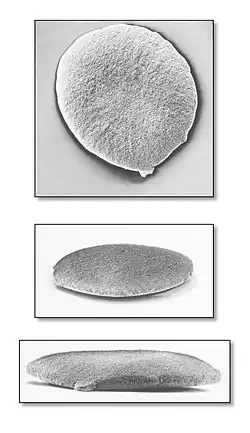

Lékaři nebo jiní zdravotníci obvykle používají 3 laboratorní techniky na diagnostiku kapavky: barvicí vzorky přímo na bakterii, detekce bakteriálních genů nebo DNA v moči a růst bakterií v laboratorních kulturách. Mnoho doktorů preferuje použití víc než jednoho testu pro zvýšení přesnosti diagnostiky.

Barvicí test zahrnuje výtěr výtoku z penisu nebo cervixu. Vzorek se umístí na sklíčko a obarví, lékař pak výsledek prohlédne pod mikroskopem. Tento test je spolehlivý u mužů, u žen nelze negativní výsledek považovat za průkazný (asi polovina infikovaných pacientek se jeví jako negativní).

Častěji se používají močové nebo cervikální výtěry pro test detekující geny bakterie. Tyto testy jsou stejně přesné nebo ještě přesnější než kultivace bakterií a používá je mnoho lékařů.

Kultivační test zahrnuje dání vzorku výtoku do kultivační nádoby a její inkubaci na 2 dny, aby mohly bakterie růst. Citlivost tohoto testu závisí na místě, ze kterého se vzorek odebere. Kultury cervikálních vzorků detekují infekci asi na 90 procent. Lékaři mohou též vzít kulturu na detekci kapavky z hrdla. Kultury umožňují i testování na bakterie odolné vůči lékům.